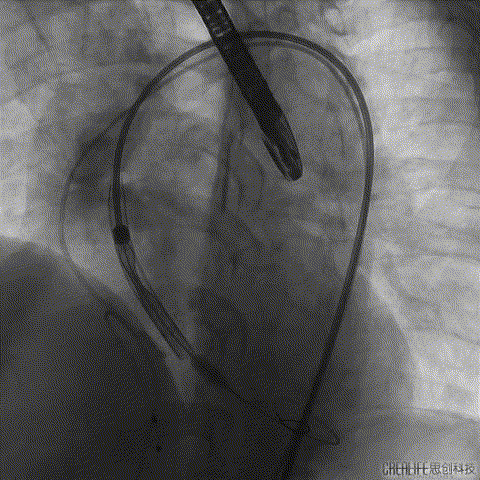

导丝跨瓣

主动脉根部造影

冠脉造影

球囊预扩